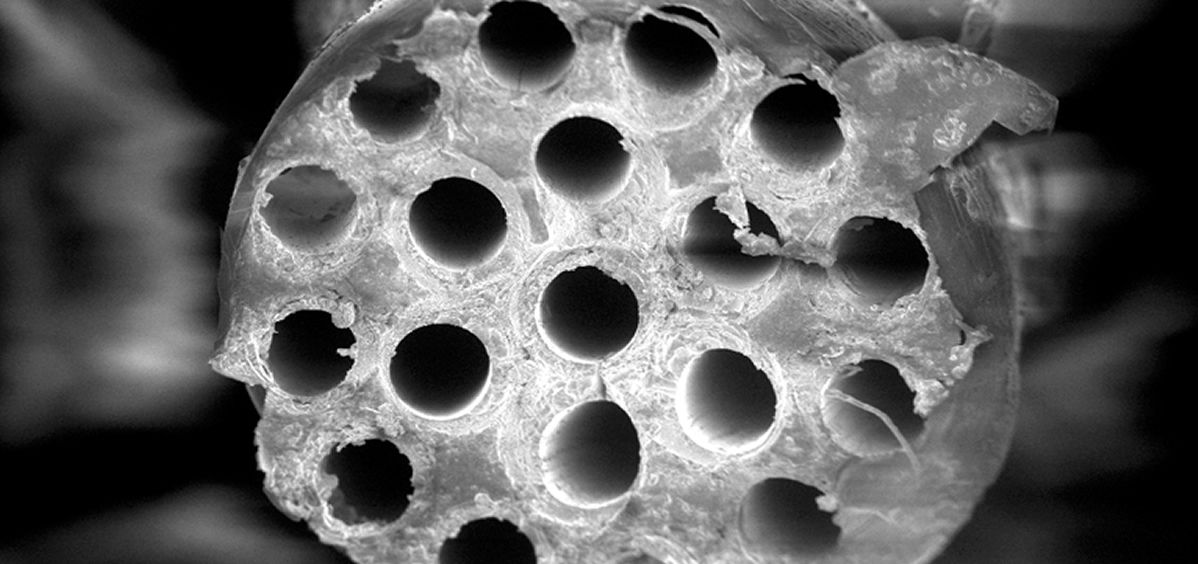

En concreto, los implantes desarrollados presentan una geometría de tubo hueco y una parte interna en forma de microcanales o fibras que permiten la proliferación de las células neuronales desde el extremo del nervio dañado al opuesto. “Esta disposición geométrica es la que hace posible la proliferación celular en el mismo fascículo del nervio, pero además consigue evitar un crecimiento descontrolado de los axones, los ejes o prolongaciones de las neuronas que tienen la importante misión de transmitir los impulsos nerviosos de una célula a otra”, añade Merino.